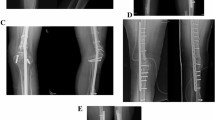

The bone tumor was excised en bloc (Free freezing procdure, Fig. 4) or with a pedicle to the healthy bone (Pedicle freezing procedure, Fig. 5) approximately 3 cm from the border of the tumor using a microsurgical saw or T-saw. The excised specimen’s soft tissues were removed on another operation table or with the healthy tissues being carefully protected using surgical sheets, and the tumor inside the bone was curetted before freezing. The curetted bone was frozen for 20 min in liquid nitrogen that was stored in sterilized flask, and then thawed at room temperature for 15 min, and in a solution of 0.3% iodine and distilled water for another 15 min. The frozen autograft was fixed to the residual healthy bone on the original site with double or triple locking plates, or intramedullary nail, or with a composite prosthesis using polymethyl methacrylate. The surgical procedures were not changed according to the histological subtype.

Free freezing procedure. The bone tumor is excised en bloc with an adequate margin. After curettage inside the bone specimen and removal of the surrounding soft tissue, the bone specimen was immersed and frozen for 20 min in liquid nitrogen. After thawing, the devitalized bone was fixed to the residual healthy bone on the original site with double locking plates.

Pedicle freezing procedure. The bone tumor is excised with a pedicle to the healthy bone with an adequate margin. After curettage inside the tumor-bearing bone and removal of the surrounding soft tissue, the remaining bone was turned upside down, and then immersed and frozen for 20 min in liquid nitrogen. After thawing, the devitalized bone was fixed to the residual healthy bone on the original site with double locking plates.